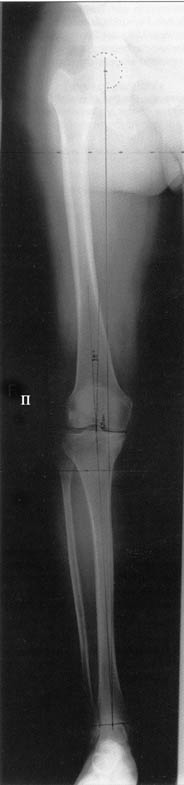

Большая просьба прокомментировать прилагавшиеся снимки. Видно, что сделано что-то красивое, но не совсем понятно, по какому поводу, как рассчитывалась коррекция, и что именно сделано.

Поводом для проведения всех корригирующих остеотомий у исследуемых пациентов служил гонартроз 1-3 стадии, косметическая коррекция в большинстве случаев являлась вторичной.

Хотя любого больного она не в меньшей степени интересовала. При всех видах остеотомий обязательным требованием являлась восстановление баланса пассивных и динамических сил путем восстановления оси конечности, стабильности связочного аппарата и контроля над мышечной активностью при осевой нагрузке. Как правило, учитывалась сохранность гиалинового хряща на компенсирующем нагрузку мыщелке бедра или большеберцовой кости. Предоперационное планирование осуществляли с поднагрузочных рентгенограмм обоих конечностей.

Дополнительными методами диагностики являлось измерение внутрикостного давления в зоне гипернагрузки и радионуклидные исследования нуклидами технеция. Применялись различные варианты остеотомий на различных сегментах. Для коррекции варусной-торсионной деформации:

высокие плюс, минус остеотомии большеберцовой кости,косая остеотомия малоберцовой. Для коррекции вальгусной деформации применялась плюс, минус надмыщелковая остеотомия бедренной кости. Фиксацию при высокой подмыщелковой остеотомии производили уникальной клинковой пластиной и тяговыми кортикальными винтами. Угол коррекции выставлялся

специальным угломером и направителем.

Поделитесь, пожалуйста, опытом, как Вам удается выполнять такие качественные рентгеновские снимки всей ноги полностью? На трех кассетах одновременно? Стыки кассет обычно <крадут> 1-2 см изображения. На снимке Вашего пациента <украденных> участков нет!

Качественные под нагрузочные рентгеновские снимки, получаются благодаря современному рентгеновскому оборудованию фирмы SIEMENS, (подробности могу уточнить у рентгенологов), а качественно стыковать (прозрачный скотч) научились с годами, но это для публикаций, для работы достаточно скрепить степлером по анатомическим осям с учетом толщины диафизов и грамотно расчертить. Пособие с удовольствием отправлю.